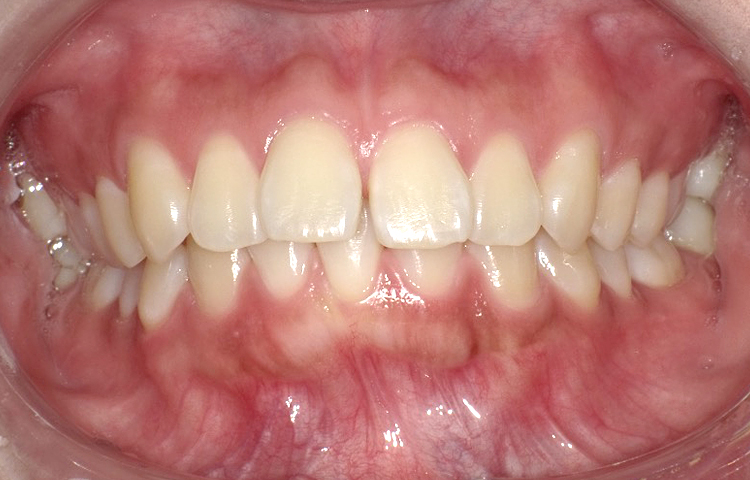

症例2

治療前

治療後

| 主訴 | 上の前歯のガタつきが気になるので前歯だけ綺麗にして欲しい |

|---|---|

| 治療 期間 |

約6ヶ月 |

| 治療費 | 165,000円(税込)/調整費用別途 |

| 治療 内容 |

上の前歯部にワイヤーを着けて進めていく、プチ矯正で施術。 |

| 治療の リスク |

見た目を綺麗にする目的で短期間で仕上げる為噛み合わせは矯正しない。 |